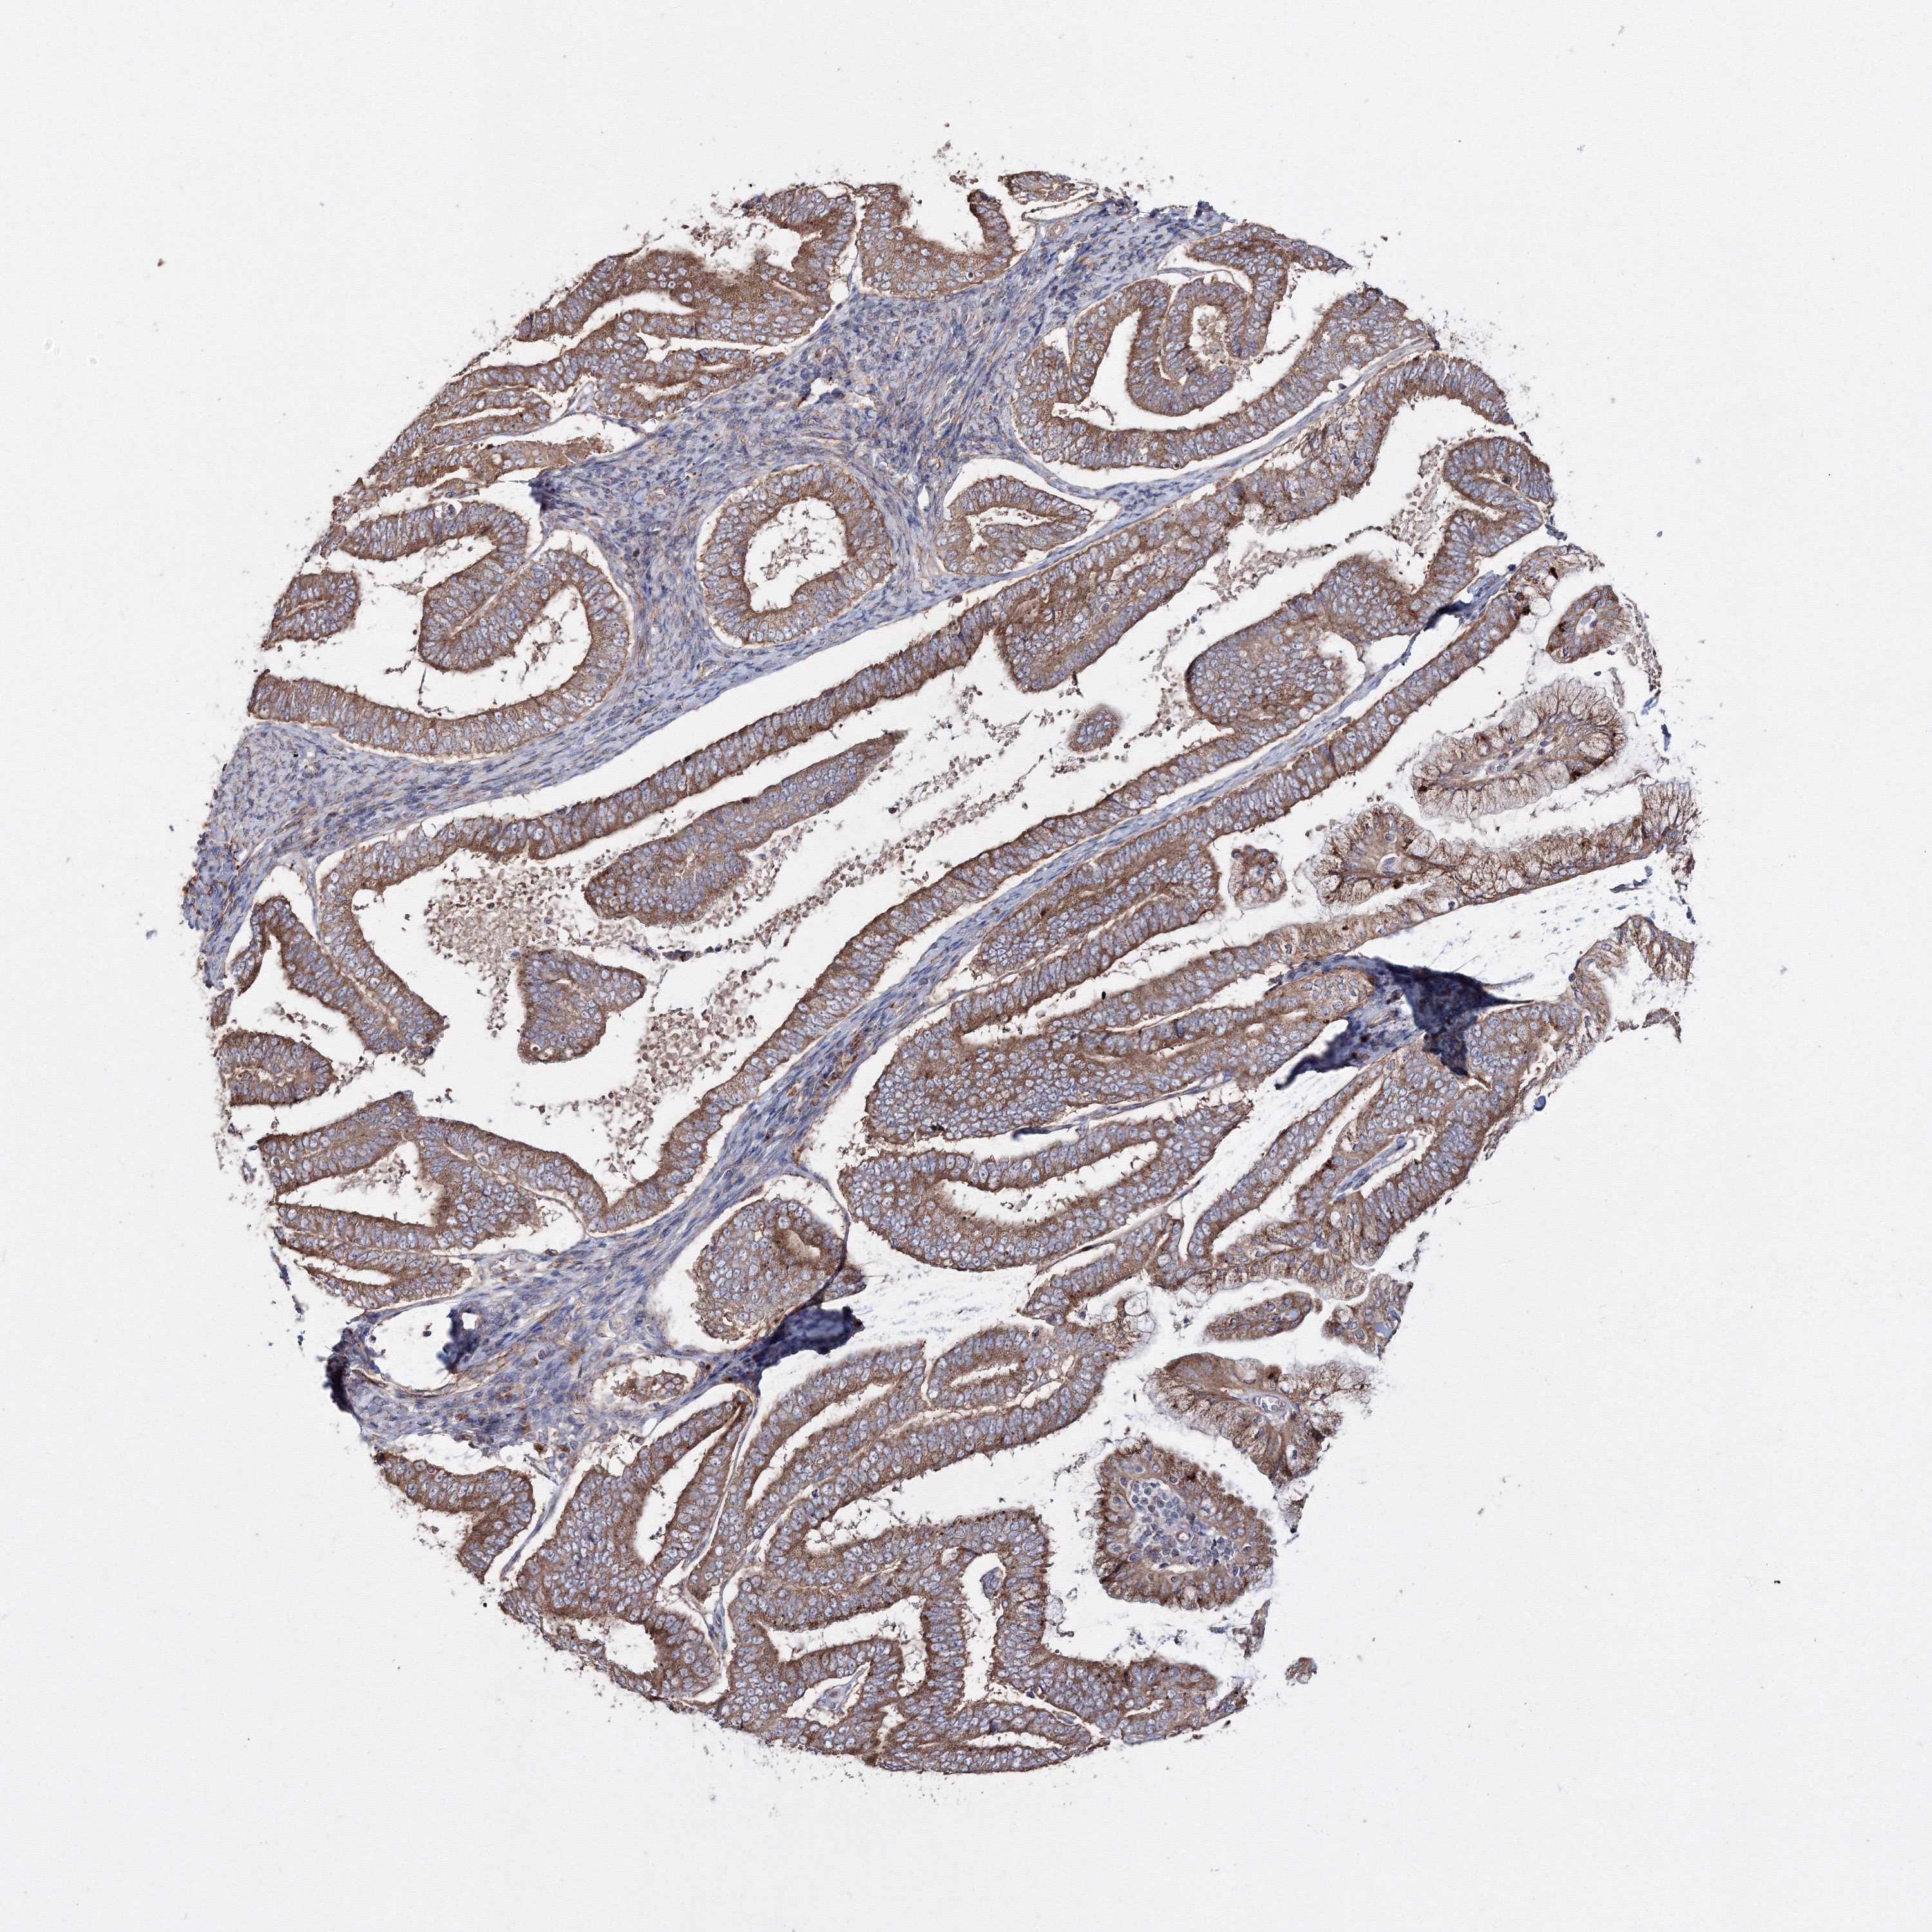

ENDOMETRIAL CANCER - Protein expressioni

A mouse-over function shows sample information and annotation data. Click on an image to view it in a full screen mode. Samples can be filtered based on level of antibody staining by selecting one or several of the following categories: high, medium, low and not detected. The assay and annotation is described here.

Note that samples used for immunohistochemistry by the Human Protein Atlas do not correspond to samples in the TCGA dataset.

Antibody stainingi

Antibody staining in the annotated cell types in the current human tissue is reported as not detected, low, medium, or high, based on conventional immunohistochemistry profiling in selected tissues. This score is based on the combination of the staining intensity and fraction of stained cells.

Each image is clickable and will lead to virtual microscopy that enables deeper exploration of all samples and also displays staining intensity scores, fraction scores and subcellular localization as well as patient and tissue information for each sample.

Antibody HPA037525

Antibody HPA037526

Staining

High

Medium

Low

Not detected

Intensity

Strong

Moderate

Weak

Negative

Quantity

>75%

75%-25%

<25%

None

Location

Nuclear

Cytoplasmic/membranous

Cytoplasmic/membranous,nuclear

Adenocarcinoma, NOS

Adenoma, NOS